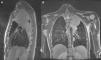

Se describe un caso inusual, debido a la edad y a la ausencia de antecedentes, de un paciente de 17años que comenzó con tos persistente no productiva, sin otra sintomatología, que no mejoró pese al tratamiento antibiótico y analgésico. Su analítica reveló una anemia microcítica hipocrómica, trombocitosis y PCR elevada. En la radiografía se identificó una masa multilobulada que la TC torácica describe como una masa sólida heterogénea de 9cm en el lóbulo superior izquierdo. En la RMN se apreciaba atelectasia del parénquima pulmonar circundante, definiendo la masa como extrapulmonar y derivada de la pleura, que además infiltraba el mediastino, rodeando parcialmente la arteria subclavia izquierda en el origen (fig. 1). No presentaba cambios endobronquiales y los cultivos de BAS fueron negativos. Se completó el estudio con una PET que evidenció hipermetabolismo de la masa con SUV máximo de 8,55, sin captación en el mediastino.